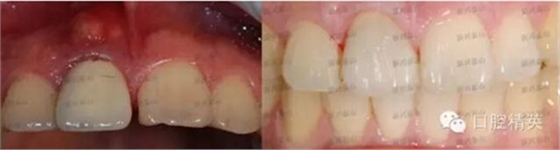

這是一個月前就診的患者,右上中切牙唇側(cè)牙齦有一個大膿包。在照片上可以看到烤瓷牙非常不美觀,一眼就能看出是假的,在前牙的位置,非常明顯,兩牙間還有很大的縫隙,顯得人比較呆板。

去掉烤瓷冠,去掉松動老式螺紋固位釘,其內(nèi)大量的腐爛牙質(zhì),治療之后,剩余牙體很少,如上圖所見。根管治療后,牙齒健康,膿包消失,可以進行后續(xù)的治療,讓患者拾回自信。

看看最后的成果吧。

怎么樣,真的是一次真實的蛻變吧!

牙齒在制作時花了點心思,既關(guān)閉了前牙縫隙,又沒有使這顆牙變得很大,患者非常滿意,很高興。

對比一下前后,視覺沖擊一下吧。

照片角度拍攝有些不一樣,但是變化還是非常明顯的。,右上中切牙唇側(cè)膿包還有點印跡,因個體的差異,慢慢會完全吸收,需要時間。